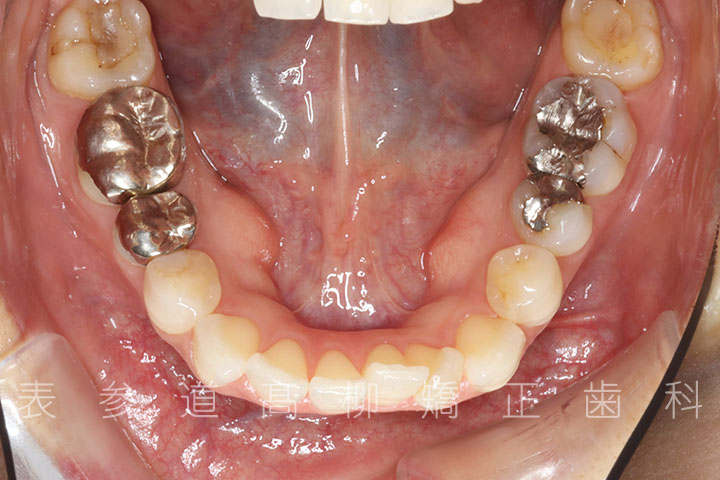

上下4本第二小臼歯抜歯症例

口呼吸と舌癖で前歯が咬み合わない患者様の症例をご紹介いたします。

治療経過

術前術後の比較